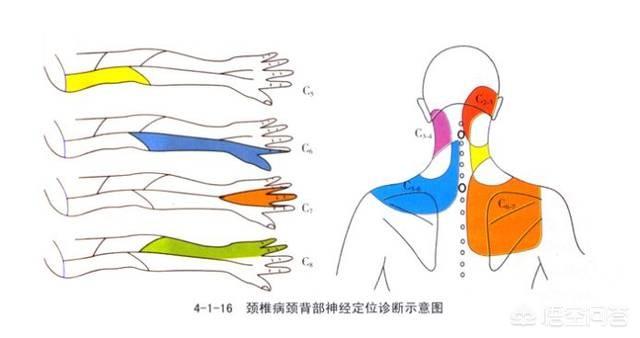

指の知覚神経は頸髄から神経根に分かれ、頸部腋窩で腕神経叢を形成し、上腕と前腕を通って橈骨神経、正中神経、尺骨神経となり、手と指に分布する末梢神経となる。

頚髄神経根を分割し、頸部に形成する。腕神経叢分ける橈骨神経、正中神経、尺骨神経経絡は上腕と前腕を等距離に通過し、最終的に頚椎となる。末梢神経手と指に分布している。そのため、指先のしびれは必ず上記の神経に問題がある。

頚椎の肥大や過形成、頚椎椎間板の変性やヘルニアは、頚神経根や頚髄を圧迫し、片側または両側の手指のしびれや痛みを誘発し、それが次第に上腕や前腕に進展し、上肢の運動障害にまで至ることがある。

如中高年特に指先のしびれ。夜間就寝中に悪化する多くは頚椎症が原因である。頚椎症は中高年に多い。骨棘頚椎症の場合、夜寝ている間に肥大した骨によって頚椎神経が圧迫刺激を受け、それが症状を引き起こす。

指先のしびれ、まずしびれの場所を見てください。左右対称か?それとも特定の指がしびれるのか、考慮すべき点は異なる!

2.片側限局性のしびれでは、尺骨神経、橈骨神経、正中神経の損傷、胸郭出口症候群、頸椎症など、考慮すべき疾患が増える。

頚椎に問題がある場合、腕神経叢の神経が圧迫されると、手のしびれや手の痛みが生じ、脳への血液供給が不足し、めまいや吐き気を引き起こす深刻な引き金となります。頚椎症による手のしびれは、親指と人差し指のしびれ、小指と薬指のしびれなど、主に片側のしびれとして現れ、ボタンが結びにくい、箸が持ちにくいなど、指の柔軟性が失われます。頚椎症になると、手指のしびれだけでなく、頚部や肩の筋肉痛、上肢の放散痛などを伴うようになります。そのため、片側の手のしびれの症状が出たときには、頚椎症かどうかを警戒する必要があります。